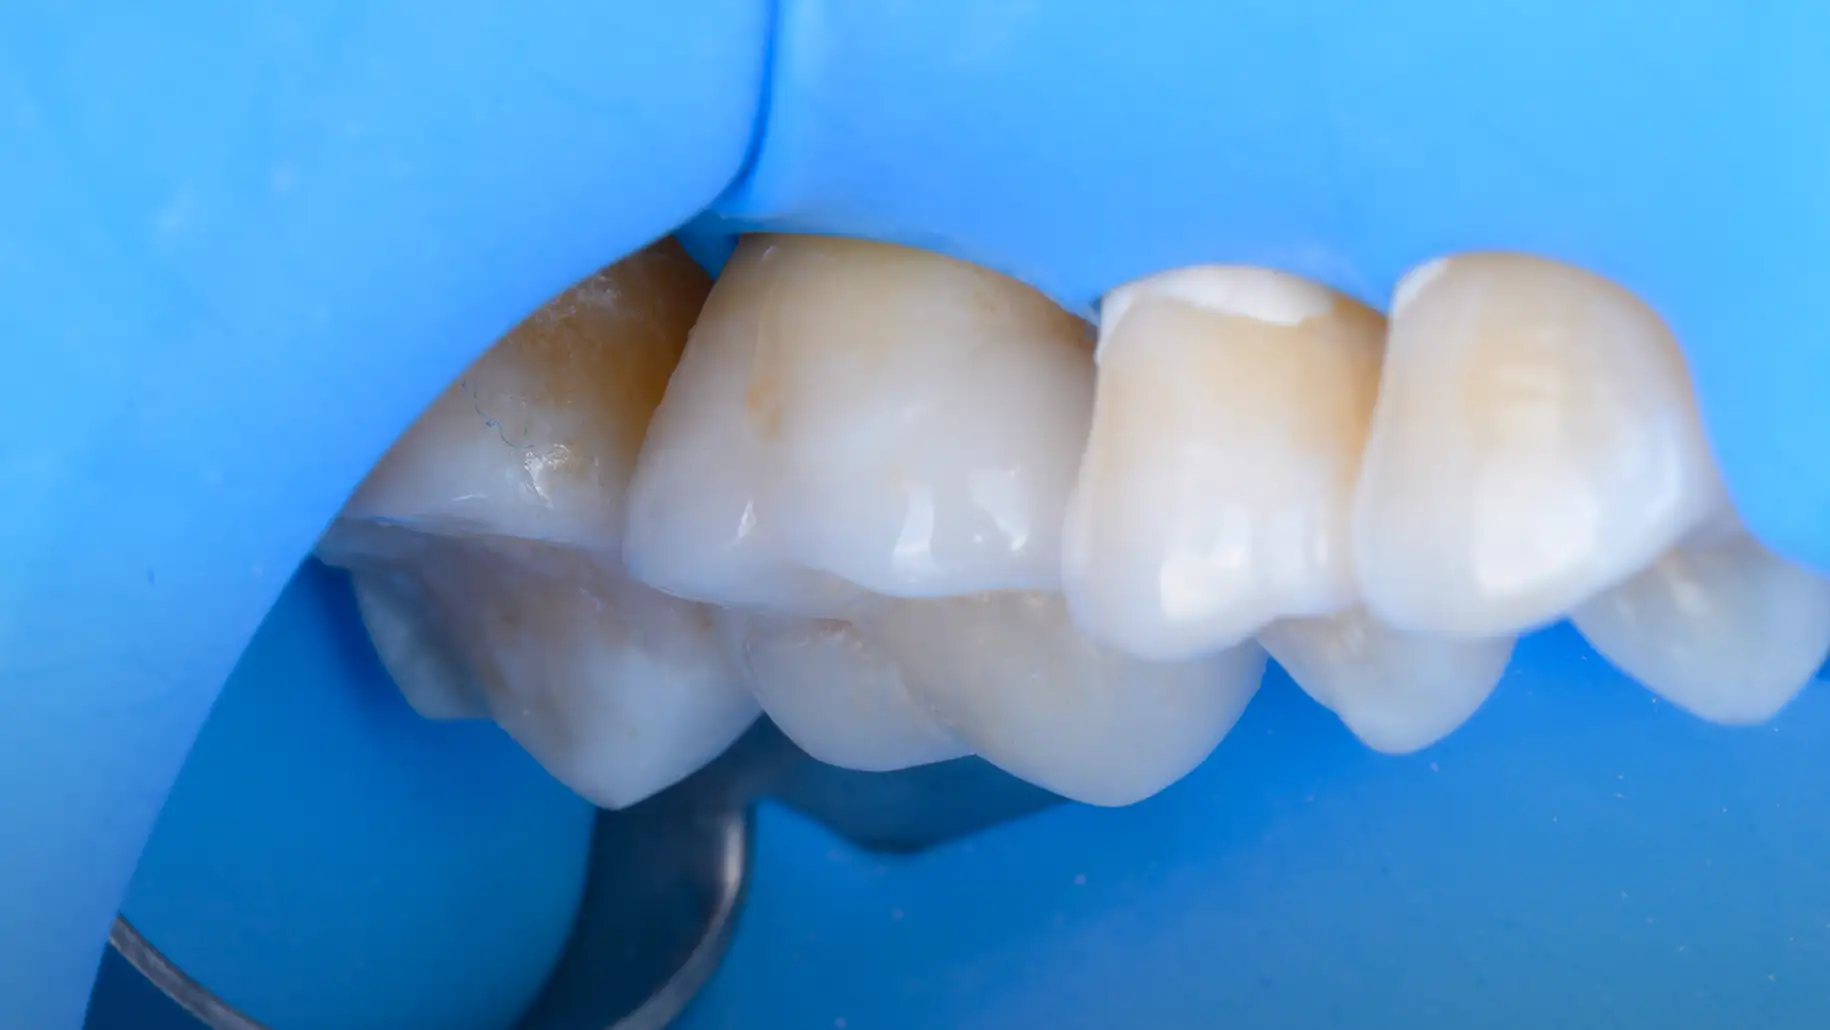

본 사례들은 동일한 조건하에 촬영된 실제 임상 사진이며, 환자분의 동의를 얻어 게재되었습니다. 의료법 제56조 제1항에 따라, 치료 결과는 환자분의 구강 환경, 식습관 및 사후 관리 정도에 따라 차이가 있을 수 있습니다. 레진 수복 치료 후 일시적인 시린 증상이 나타날 수 있으며, 시간이 흐름에 따라 수복물의 변색이나 마모, 탈락이 발생할 수 있으므로 정기적인 검진을 권장합니다.

해부학적 형태의 정밀 복원

간접 수복은 구강 외에서 수작업으로 보철물을 제작합니다. 정교하게 치아의 해부학적인 형태를 복원하고, 교합 관계를 회복시킵니다.

오차를 최소화하는 정밀한 보철 과정

정밀하게 제작된 보철물은 경계부에서의 오차를 최소화하고, 내면의 적합을 최대화하는 방향으로 제작됩니다.